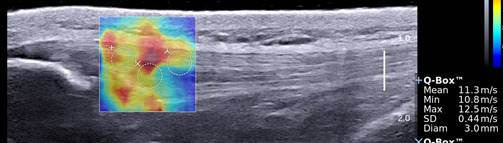

One of the many highlights of MSK research is the Sports Imaging and Intervention Research Program. It is a multi-disciplinary team striving to find effective minimally invasive treatments for common musculoskeletal tendon injuries such as tennis elbow, patellar tendinitis, Achilles tendinitis and plantar fasciitis. Using a Team Science approach to research, we incorporate innovative tools such as biomechanical sensors, special ultrasound measurements, and state-of-the-art MRI pictures to stratify disease severity and assess healing response. Our ultimate goal is to change the way we approach and treat common disabling tendon injuries so that you can return to your sport or daily lives as soon as possible.